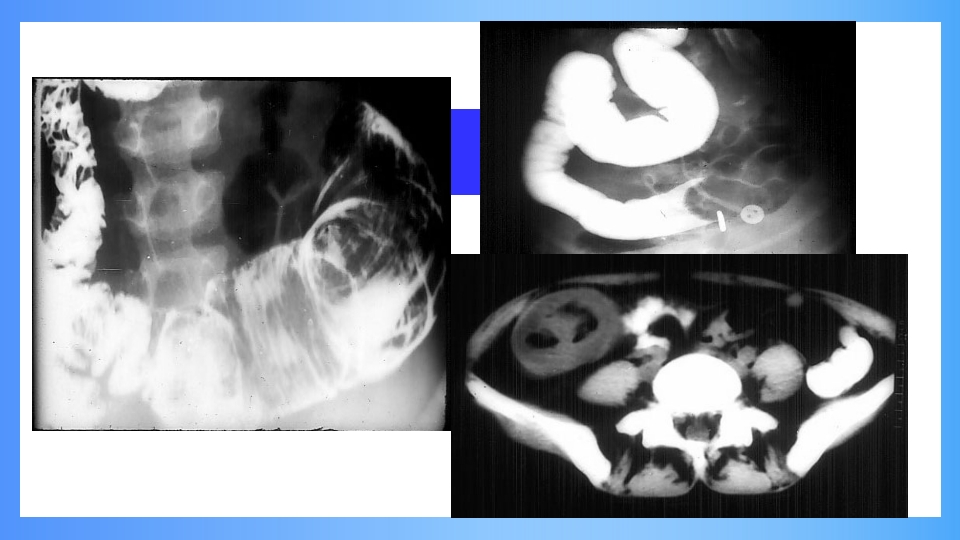

肠梗阻 intestinal obstruction 一、概述 发病情况:外科急腹症中第三位。 定义:肠内容物不能正常运行、顺利 通过肠道。 死亡率:绞窄性肠梗阻高达10%。 二、病因和分类 发病原因 机械性肠梗阻 动力性肠梗阻 血运性肠梗阻 肠壁有无血运鄣碍 绞窄性肠梗阻 单纯性肠梗阻 梗阻部位 高位和低位 梗阻程度 完全性和不全性 机械性肠梗阻mechanical obstruction 肠腔堵塞 如寄生虫、胆石、粪块、肠套叠等。 肠管受压 粘连、嵌顿疝、肠扭转和肿瘤压迫。 肠壁病变 先天性肠道闭缩、炎症狭窄、肿瘤、 医源性。 返回 返回 返回 返回 返回 返回 动力性肠梗阻 麻痹性肠梗阻(paralytic ileus) 急性弥漫性腹膜炎、腹部大手术、腹膜后血肿或感染、 低钾血症等。 痉挛性肠梗阻 ...